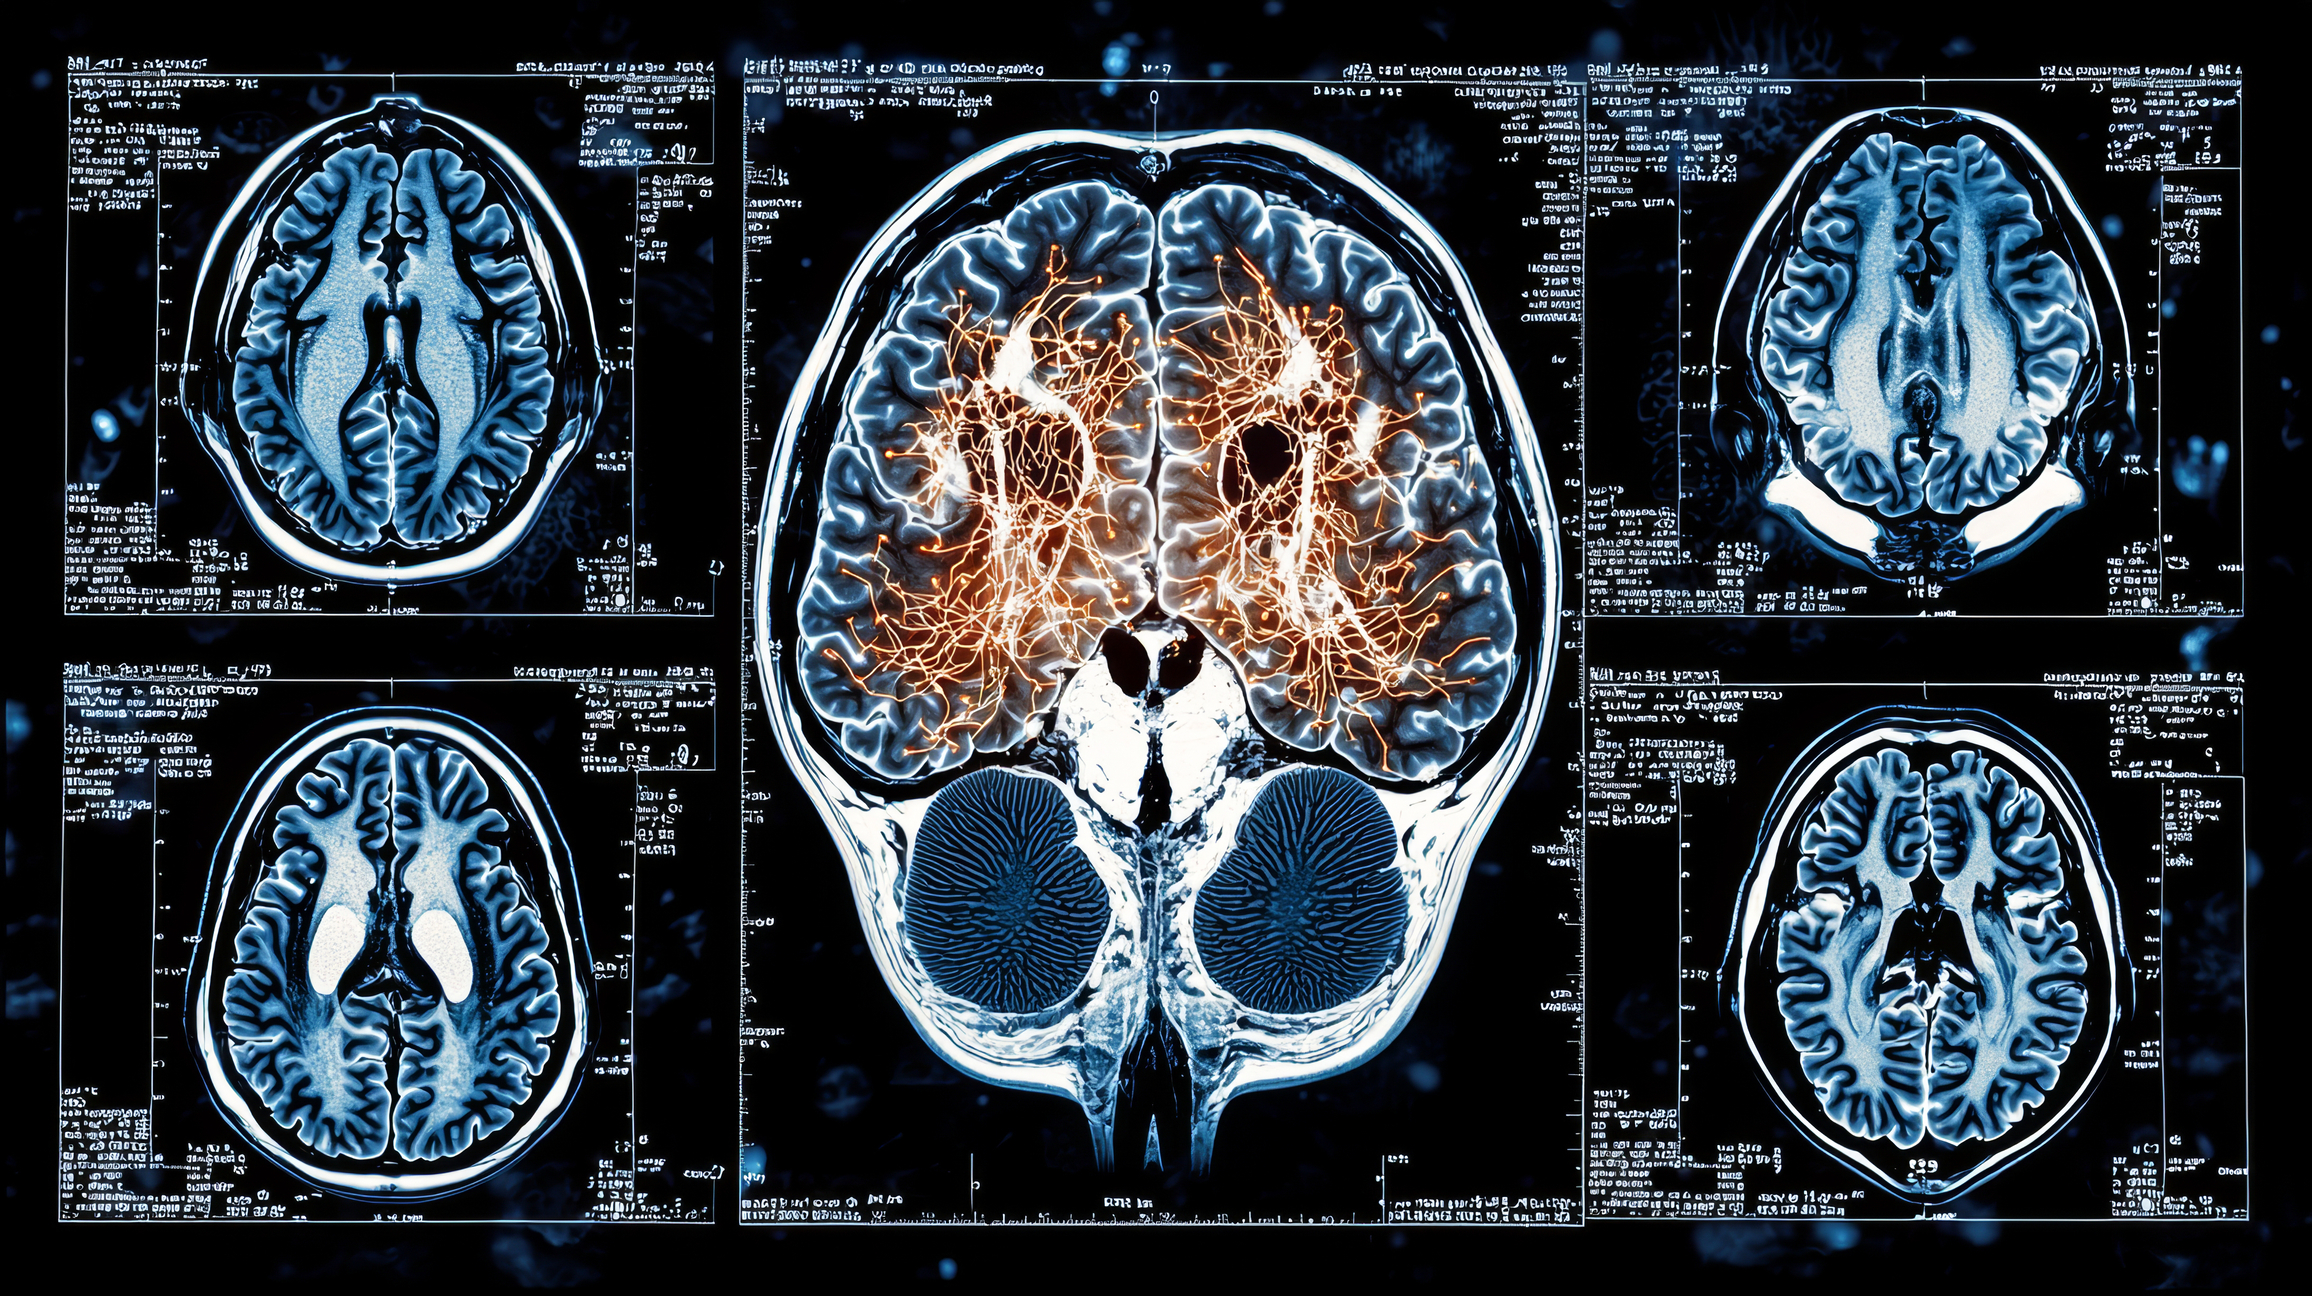

Addiction is a chronic brain disorder that affects millions globally. Traditional treatment methods, while effective for many, often rely on self-reporting, behavioural observations, and trial-and-error approaches. However, recent developments in artificial intelligence (AI) and neuroimaging are beginning to bridge gaps in understanding, offering objective insights into addiction’s neurological basis. By integrating machine learning algorithms with advanced imaging tools such as MRI, PET, and EEG, researchers and clinicians can map patterns of addiction, predict relapse, and tailor interventions to individual needs.

Neuroimaging technologies have long been used to study structural and functional brain changes associated with addiction. Functional MRI (fMRI), for example, shows how different brain regions communicate during tasks or at rest, revealing abnormalities in networks related to reward, impulse control, and decision-making.

When combined with AI, the volume of imaging data becomes manageable and clinically useful. Machine learning models can analyse complex brain scans to detect subtle patterns that might indicate susceptibility to addiction or the effectiveness of a given treatment. For instance, AI can identify changes in the prefrontal cortex that correlate with cravings or an increased risk of relapse, even before symptoms become evident.